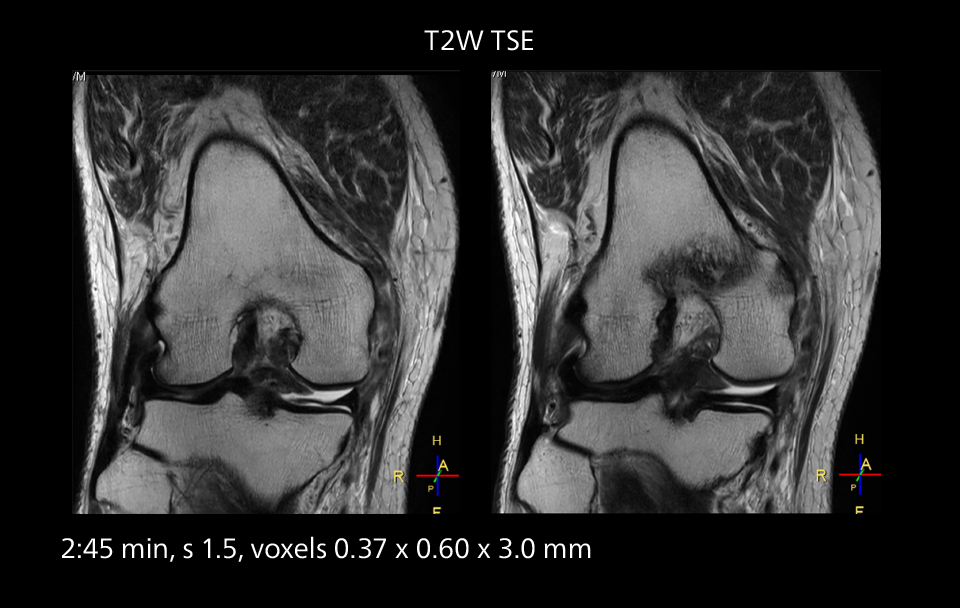

MRI of the knee

Images showing a posterior cruciate ligament (PCL) tear, a detached medial collateral ligament (MCL) on the tibial side and an intact anterior cruciate ligament (ACL). SmartPath to Elition X helped reduce scan time compared to previous imaging while maintaining resolution.

MRI of the knee

Images showing a posterior cruciate ligament (PCL) tear, a detached medial collateral ligament (MCL) on the tibial side and an intact anterior cruciate ligament (ACL). SmartPath to Elition X helped reduce scan time compared to previous imaging while maintaining resolution.

Sannodai Hospital radiologists had been very satisfied with their Ingenia 3.0T with Compressed SENSE, however after acquiring SmartPath to Elition X they have demonstrated improved image quality and even higher speeds in imaging studies throughout the body, according to Dr. Makuuchi. “Generally, we were impressed by seeing that images are very sharp and have higher SNR than we used to get with our Ingenia 3.0T system,” he notes. “We were delighted to see that high image quality can be obtained in a short time thanks to the Elition with its powerful An example of increased imaging speed is in knee studies. “There is a definite scan time reduction for T2* mFFE and proton density TSE – both of these sequences benefit from much shorter repetition times,” he reports.

gradients. Some high resolution examinations that were not possible before dueto their longer scan time, are now routinely performed with the upgraded system.”

Overall, imaging time per sequence has been reduced since the Elition X upgrade. This can help reduce the risk of patient movement and the need for rescans. “As our hospital has many elderly patients, we consider it important to obtain high-quality data in a short time,” Dr. Makuuchi says. “Shorter imaging times are also useful for accepting emergency patients, because faster emergency studies have a reduced impact on the daily examinations schedule. In emergency cases it is also important that high quality images are obtained in a short time.”